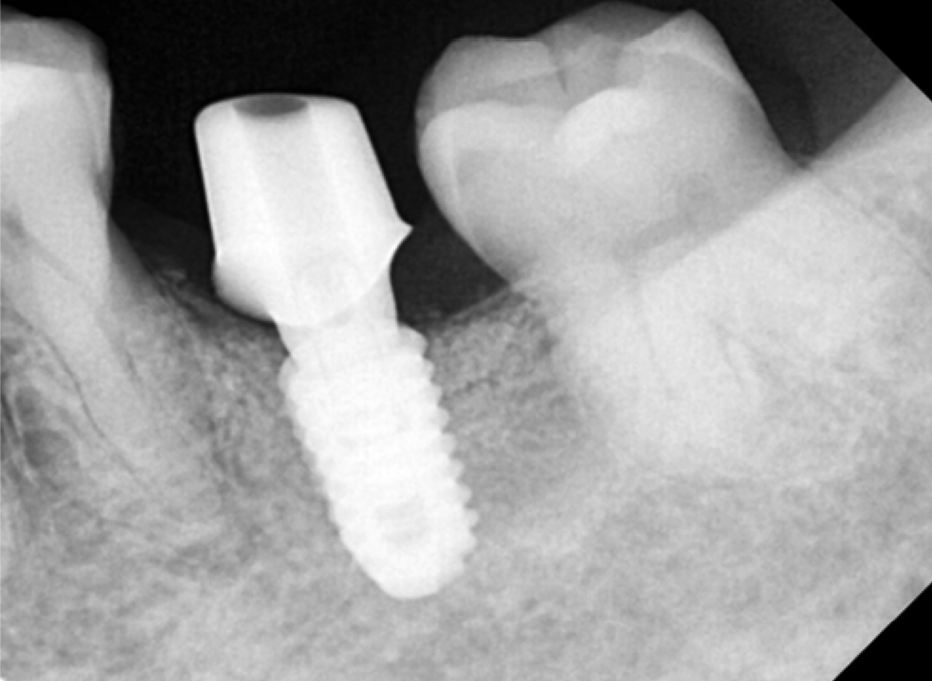

기다리는 동안 오른쪽 아래 어금니를 진행합니다.

오른쪽 아래는 발치한 지 오래되었고,

염증은 없는 상태라 뼈이식 없이 임플란트 식립을 진행하였습니다.

2개월 후 보철을 올릴 수 있을 것으로 판단하였습니다.

다행히 임플란트랑 뼈랑 잘 고정이되어 최종 보철물 인상채득을 시행했습니다.

본뜨는 나사를 연결해서 인상을 채득하면,

이렇게 기공소에서 맞춤 어버트먼트로 제작이됩니다.